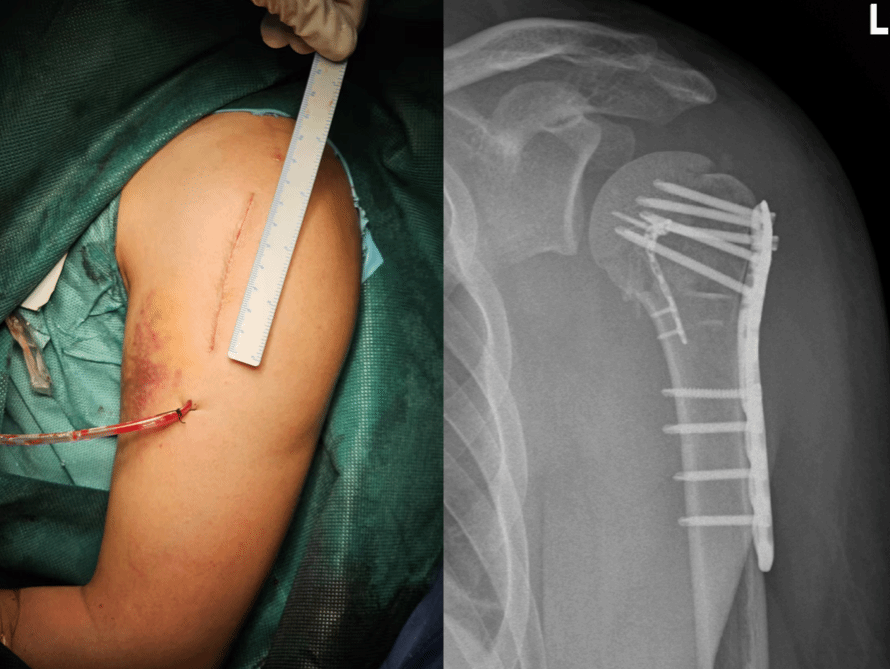

因此,王义隽团队特别制定了个性化方案——团队原创的“髓内骨距支撑钢板”固定技术。这项技术的核心创新在于,巧妙利用了骨折块之间已形成的“天然手术通道”,“传统方法多从外侧进行固定,往往难以重建肱骨内侧这一关键的‘力学核心’,而我们的思路是‘由内而外’——借助骨折本身形成的通道,将特制钢板植入骨髓腔内部,先在直视下精准复位并固定内侧骨距,再结合外侧钢板形成双重加固,构建一个内外协同的立体稳定系统。”术后,张先生疼痛明显减轻,数十天后便开始康复锻炼。

据悉,这一技术通过“髓内支撑+外侧锁定”的双重固定模式,与传统钢板相比整体结构强度提升92%,显著提升稳定性与愈合率,并降低手术操作难度,尤其适用于张先生这类移位明显、伴有骨质疏松征象的复杂骨折。

更重要的是,这一方式能够大幅降低患者的治疗费用,王义隽介绍,一台关节置换手术的费用约为十万元,而采取髓内骨距支撑钢板固定技术仅需约两千元。同时,手术还可经同一切口一并修复损伤的肩袖组织,最大程度保留关节的动力功能,使得患者术后肩关节活动度与肌力恢复往往优于传统手术,同时减少对骨骼血运的破坏,为骨折愈合创造更有利的生物学环境,患者术后疼痛较轻,并发症少,更利于康复。